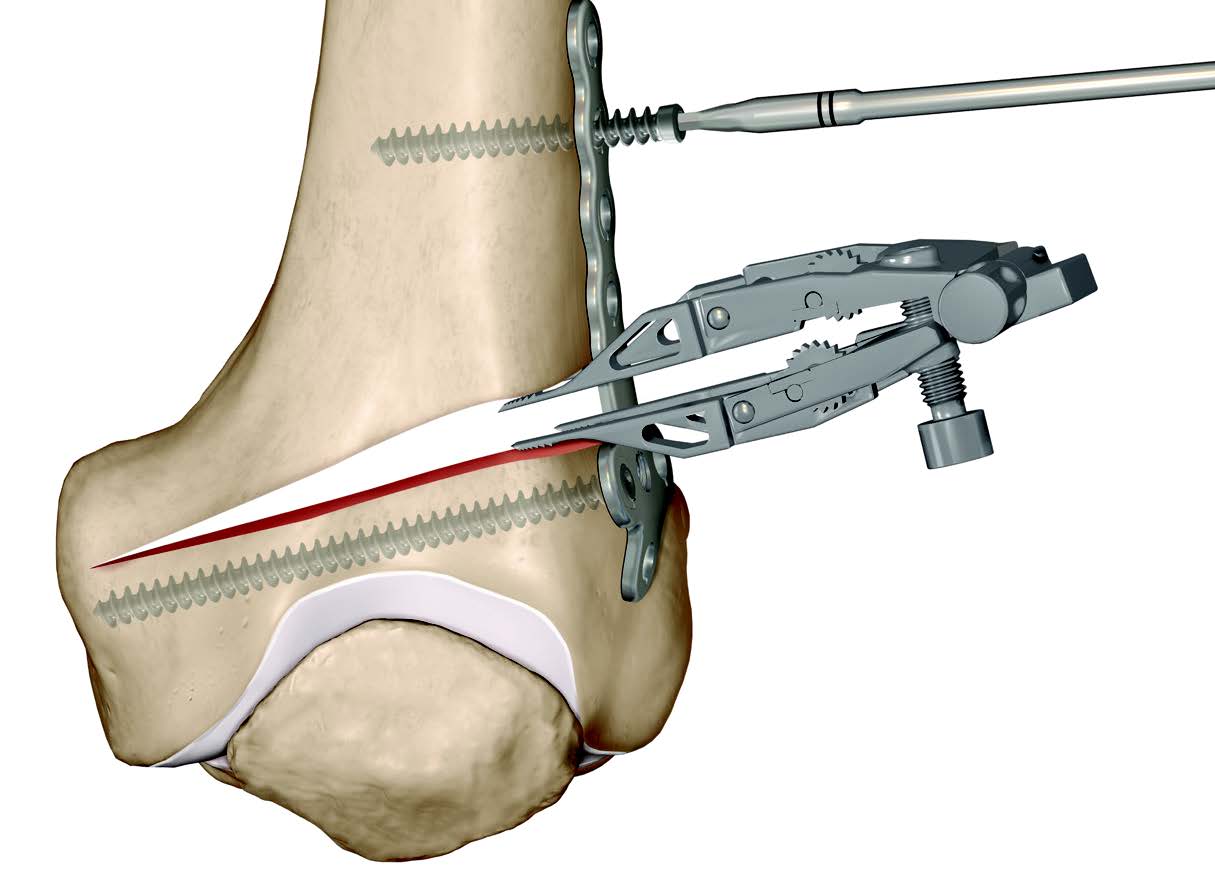

Biplanar Osteotomy

Concept

Create anterior flange

- minimum 1 cm deep

- 3 - 4 cm long

Advantage

Increased mechanical stability / controls rotation

Increases surface area for healing

Lateral Opening Wedge Biplanar Technique

Medial Closing Wedge Biplanar Technique